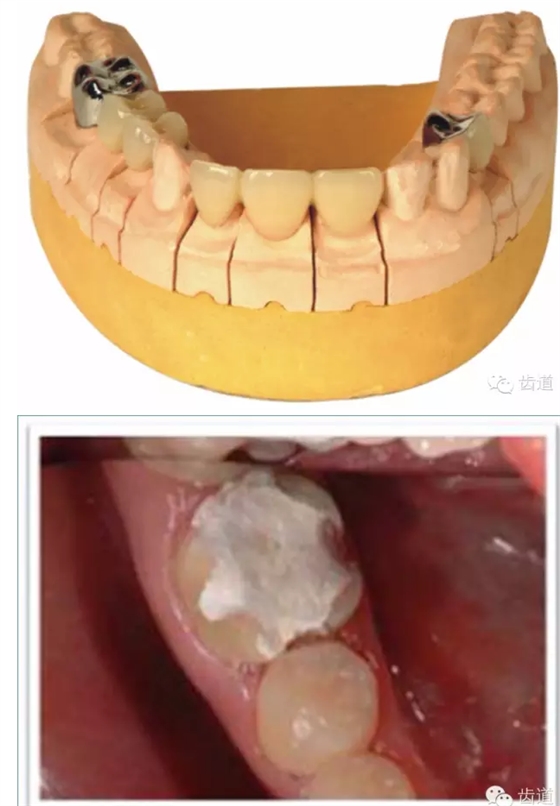

l多個(gè)基牙時(shí)就位道的調(diào)節(jié)

l實(shí)際備牙產(chǎn)生的問(wèn)題

正壓力:即修復(fù)體的密貼程度(小于0.2mm)

表面粗糙程度

牙的外形及洞形的幾何形狀:主要是牙體制備出一定聚合角度產(chǎn)生的阻擋作用